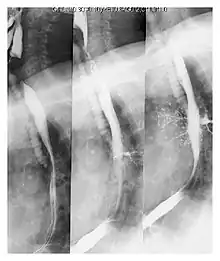

| Upper gastrointestinal series at the level of the esophagus, showing pulmonary aspiration of the radiocontrast agent | |

Pulmonary aspiration is the entry of material such as pharyngeal secretions, food or drink, or stomach contents from the oropharynx or gastrointestinal tract, into the larynx (voice box) and lower respiratory tract, the portions of the respiratory system from the trachea (windpipe) to the lungs. A person may inhale the material, or it may be delivered into the tracheobronchial tree during positive pressure ventilation. When pulmonary aspiration occurs during eating and drinking, the aspirated material is often colloquially referred to as "going down the wrong pipe".